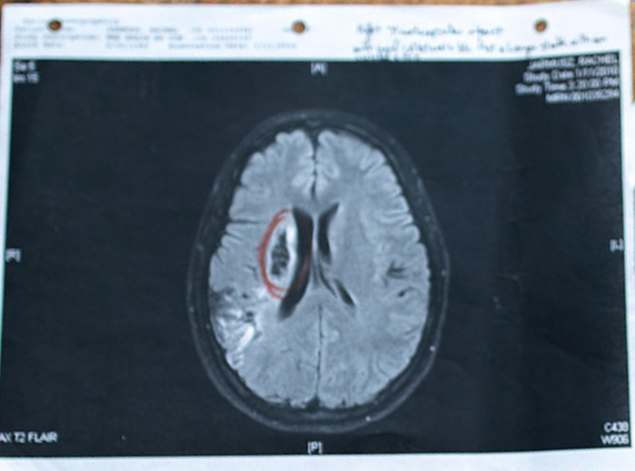

• June 12, 2009: Ischemic Stroke. Carotid artery dissection on Rollercoaster.

My YogaWill was born out of my journey using yoga as a tool for regaining strength while restoring health after a massive ischemic stroke I had in 2009, not long after giving birth to my second son. I was only 25 and refused to believe in the limitations placed on my body. I set out on an unconventional path.